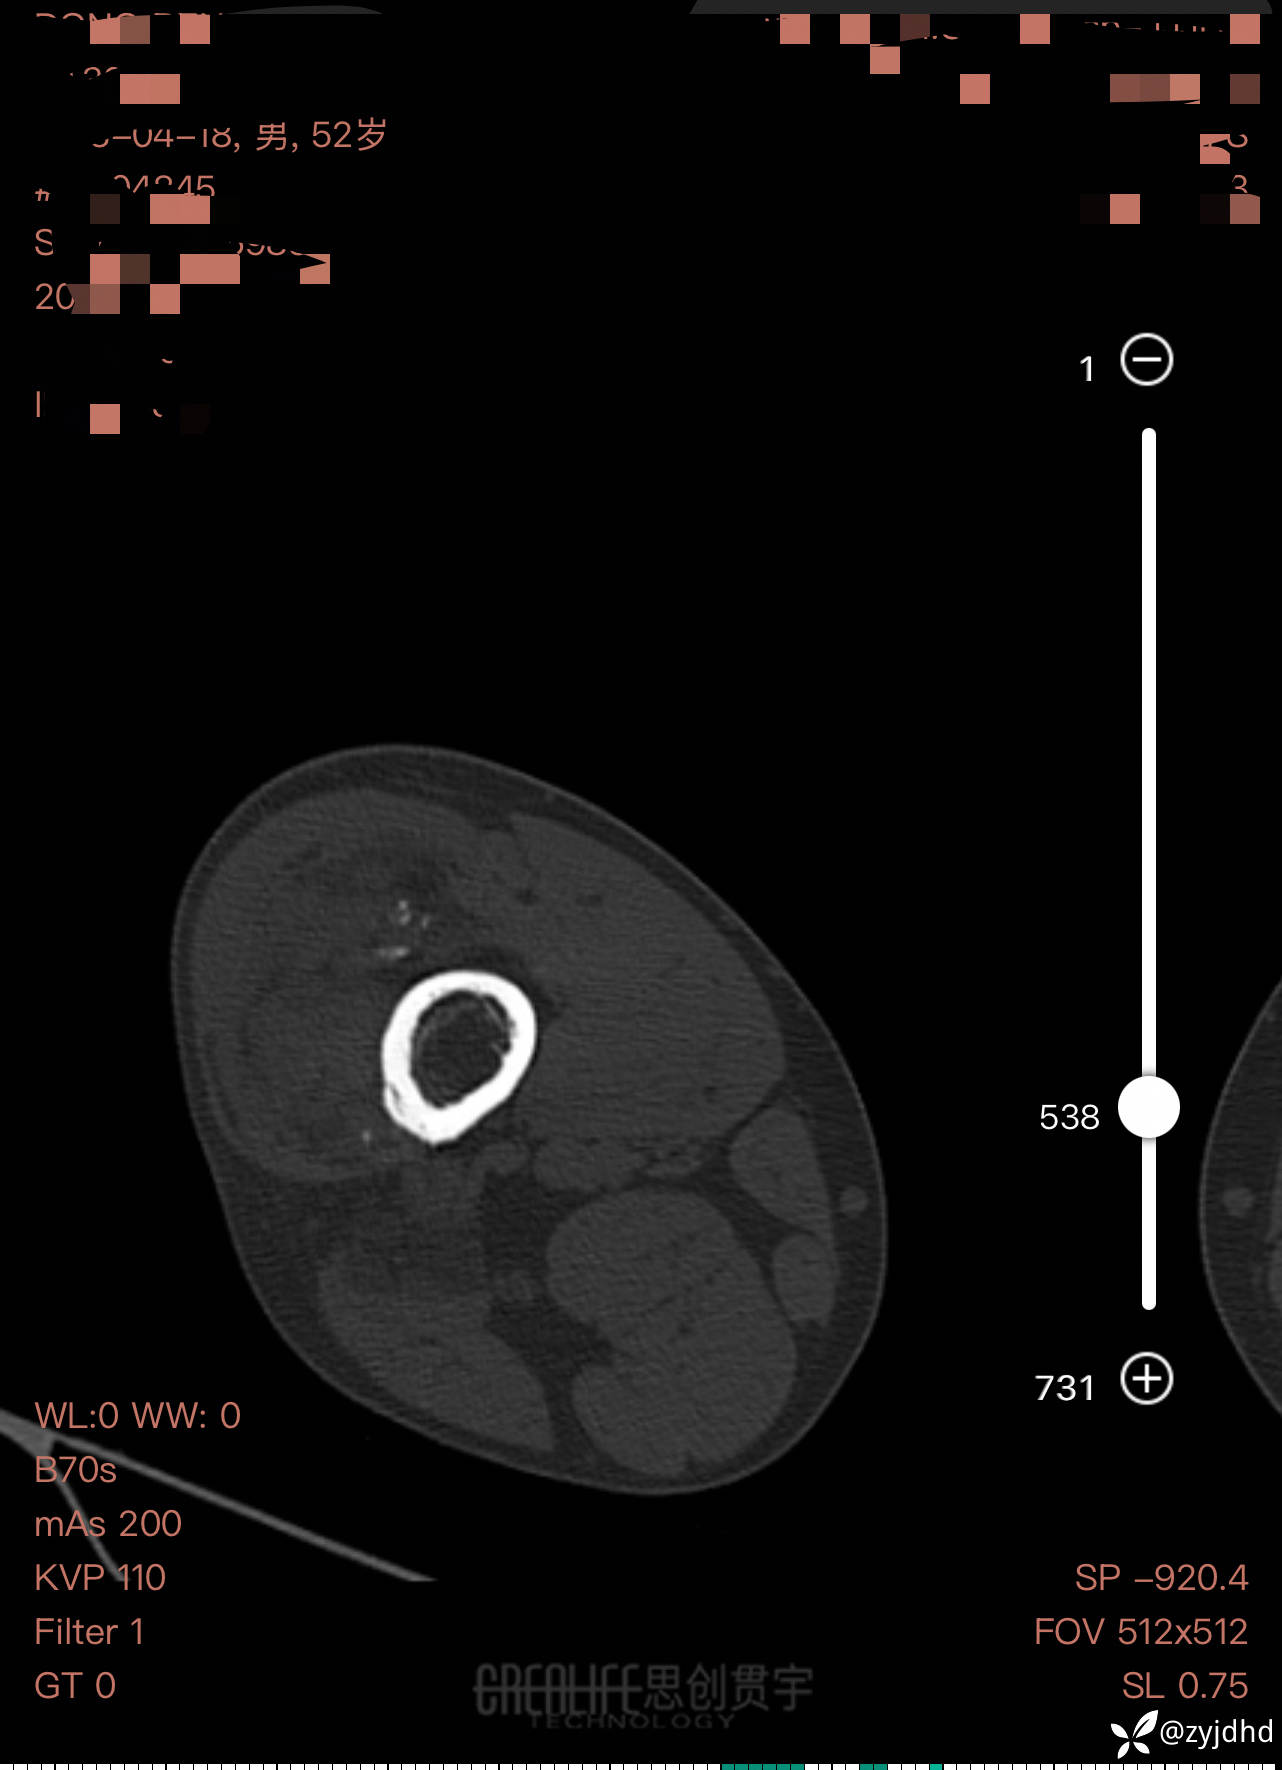

男性,发现右大腿肿物20年。